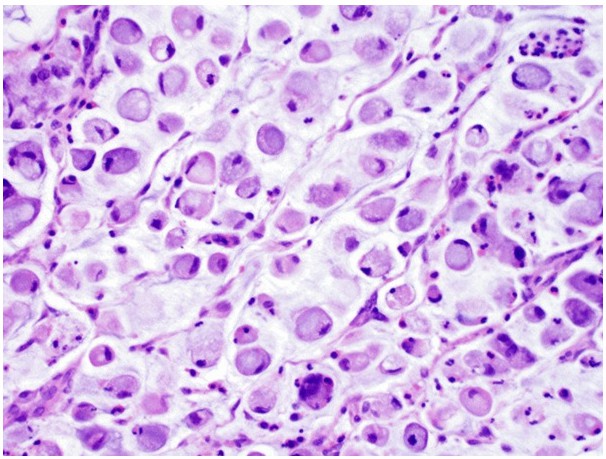

Fig.3 Signet ring cell-type bladder adenocarcinoma. (Dadhania, V., et al., 2015)Fig.3 Signet ring cell-type bladder adenocarcinoma is characterized by large intracellular mucin vacuoles that displace nuclei to the periphery. (Dadhania, V., et al., 2015)